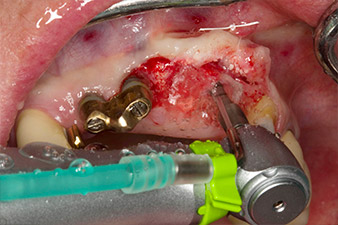

Der Alveolarknochen erweist sich an Position 22 als ausreichend dimensioniert. Die Abbildungen 2 und 4 zeigen die Implantatbett-Aufbereitung, den Gewindeschnitt und die Implantation mit dem Implantmed.

Der neue Implantologiemotor wird jeweils mit den geeigneten chirurgischen Winkelstücken von W&H verwendet.